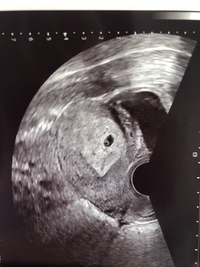

5週 胎嚢 見えない hcg高い- 妊娠5週5日(週数ほぼ正確)胎嚢確認日。 hcg 1434 だが、胎嚢確認できず。 胎嚢が見えない原因、3つの可能性 胎嚢まだが発育してなくて見えていない状態; 胎嚢が見えるには通常1000くらいの値が必要らしい。 やっぱり低いHcg。 5週目で普通は胎嚢確認できるらしいが できてないのはおかしいと焦る先生。 (排卵日のズレで見えない

正常妊娠では、着床開始後まもなくhCGが検出され始め、妊娠4週0日で血中hCG値は100~0 IU/lとなり、5週0日には約00~4000 IU/lと指数関数的に増加する。 00 IU/l以上のhCG分泌があ 23/1/25 1023 0 回答 性交日と数週が合いません。 生理開始日が12月10日なので単純計算だと今日1月25日で6週4日だと思っていたのですが、本日産婦人科で診てもらうと胎嚢し